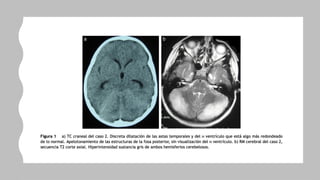

Diagnostico

• Neuroimagen

• LCR

• Laboratorio